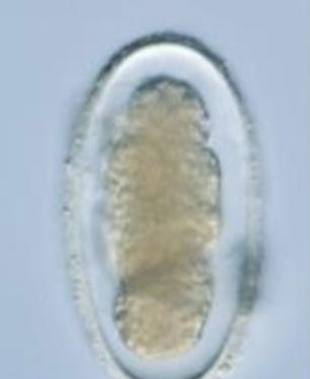

Metastrongylus spp

Ovum